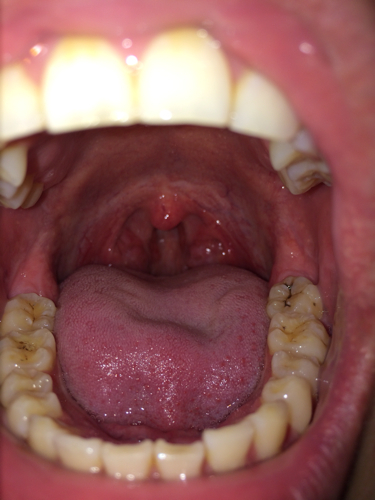

喉咙里白色的是什么东西

嗓子上有白色的东西可能与以下几种情况有关,需及时就医明确病因并针对性治疗1 扁桃体结石扁桃体表面存在隐窝,食物残渣细菌及死细胞长期积聚并钙化,会形成白色小硬块典型表现为口臭喉咙异物感或轻微疼痛,但多数情况下无明显症状...